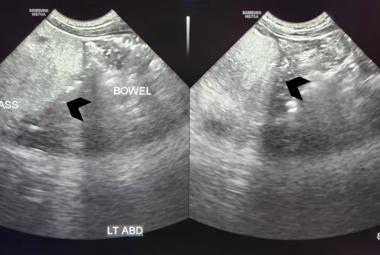

In recent years, the approach to traumatic cardiac arrest (TCA) has undergone a significant transformation, moving from what was once considered futile to a more promising and structured intervention. The European Resuscitation Council (ERC) Guidelines established a framework for the management of TCA. We presented a case of return of spontaneous circulation (ROSC) in traumatic cardiac arrest achieved by traumatic – based resuscitation adhered to this guideline. A 50-years-old man who fell from a height of 10 feet arrived at Emergency Department in cardiac arrest. Immediate cardiopulmonary resuscitation (CPR) was initiated. The patient was intubated using endotracheal intubation for airway management. Oxygen and ventilation were delivered through bag-valve-mask. Chest compressions were started, and warm intravenous fluid and blood transfusions were administered to address hypovolemia. Manual compression was applied to stop massive bleeding from the scalp and the left ear. ROSC was achieved following bilateral chest decompression. TCA algorithm had higher rate of ROSC as well as a trend towards improved survival to discharge. Practitioners should prioritise the rapid and aggressive treatment of potential reversible causes in TCA patients.